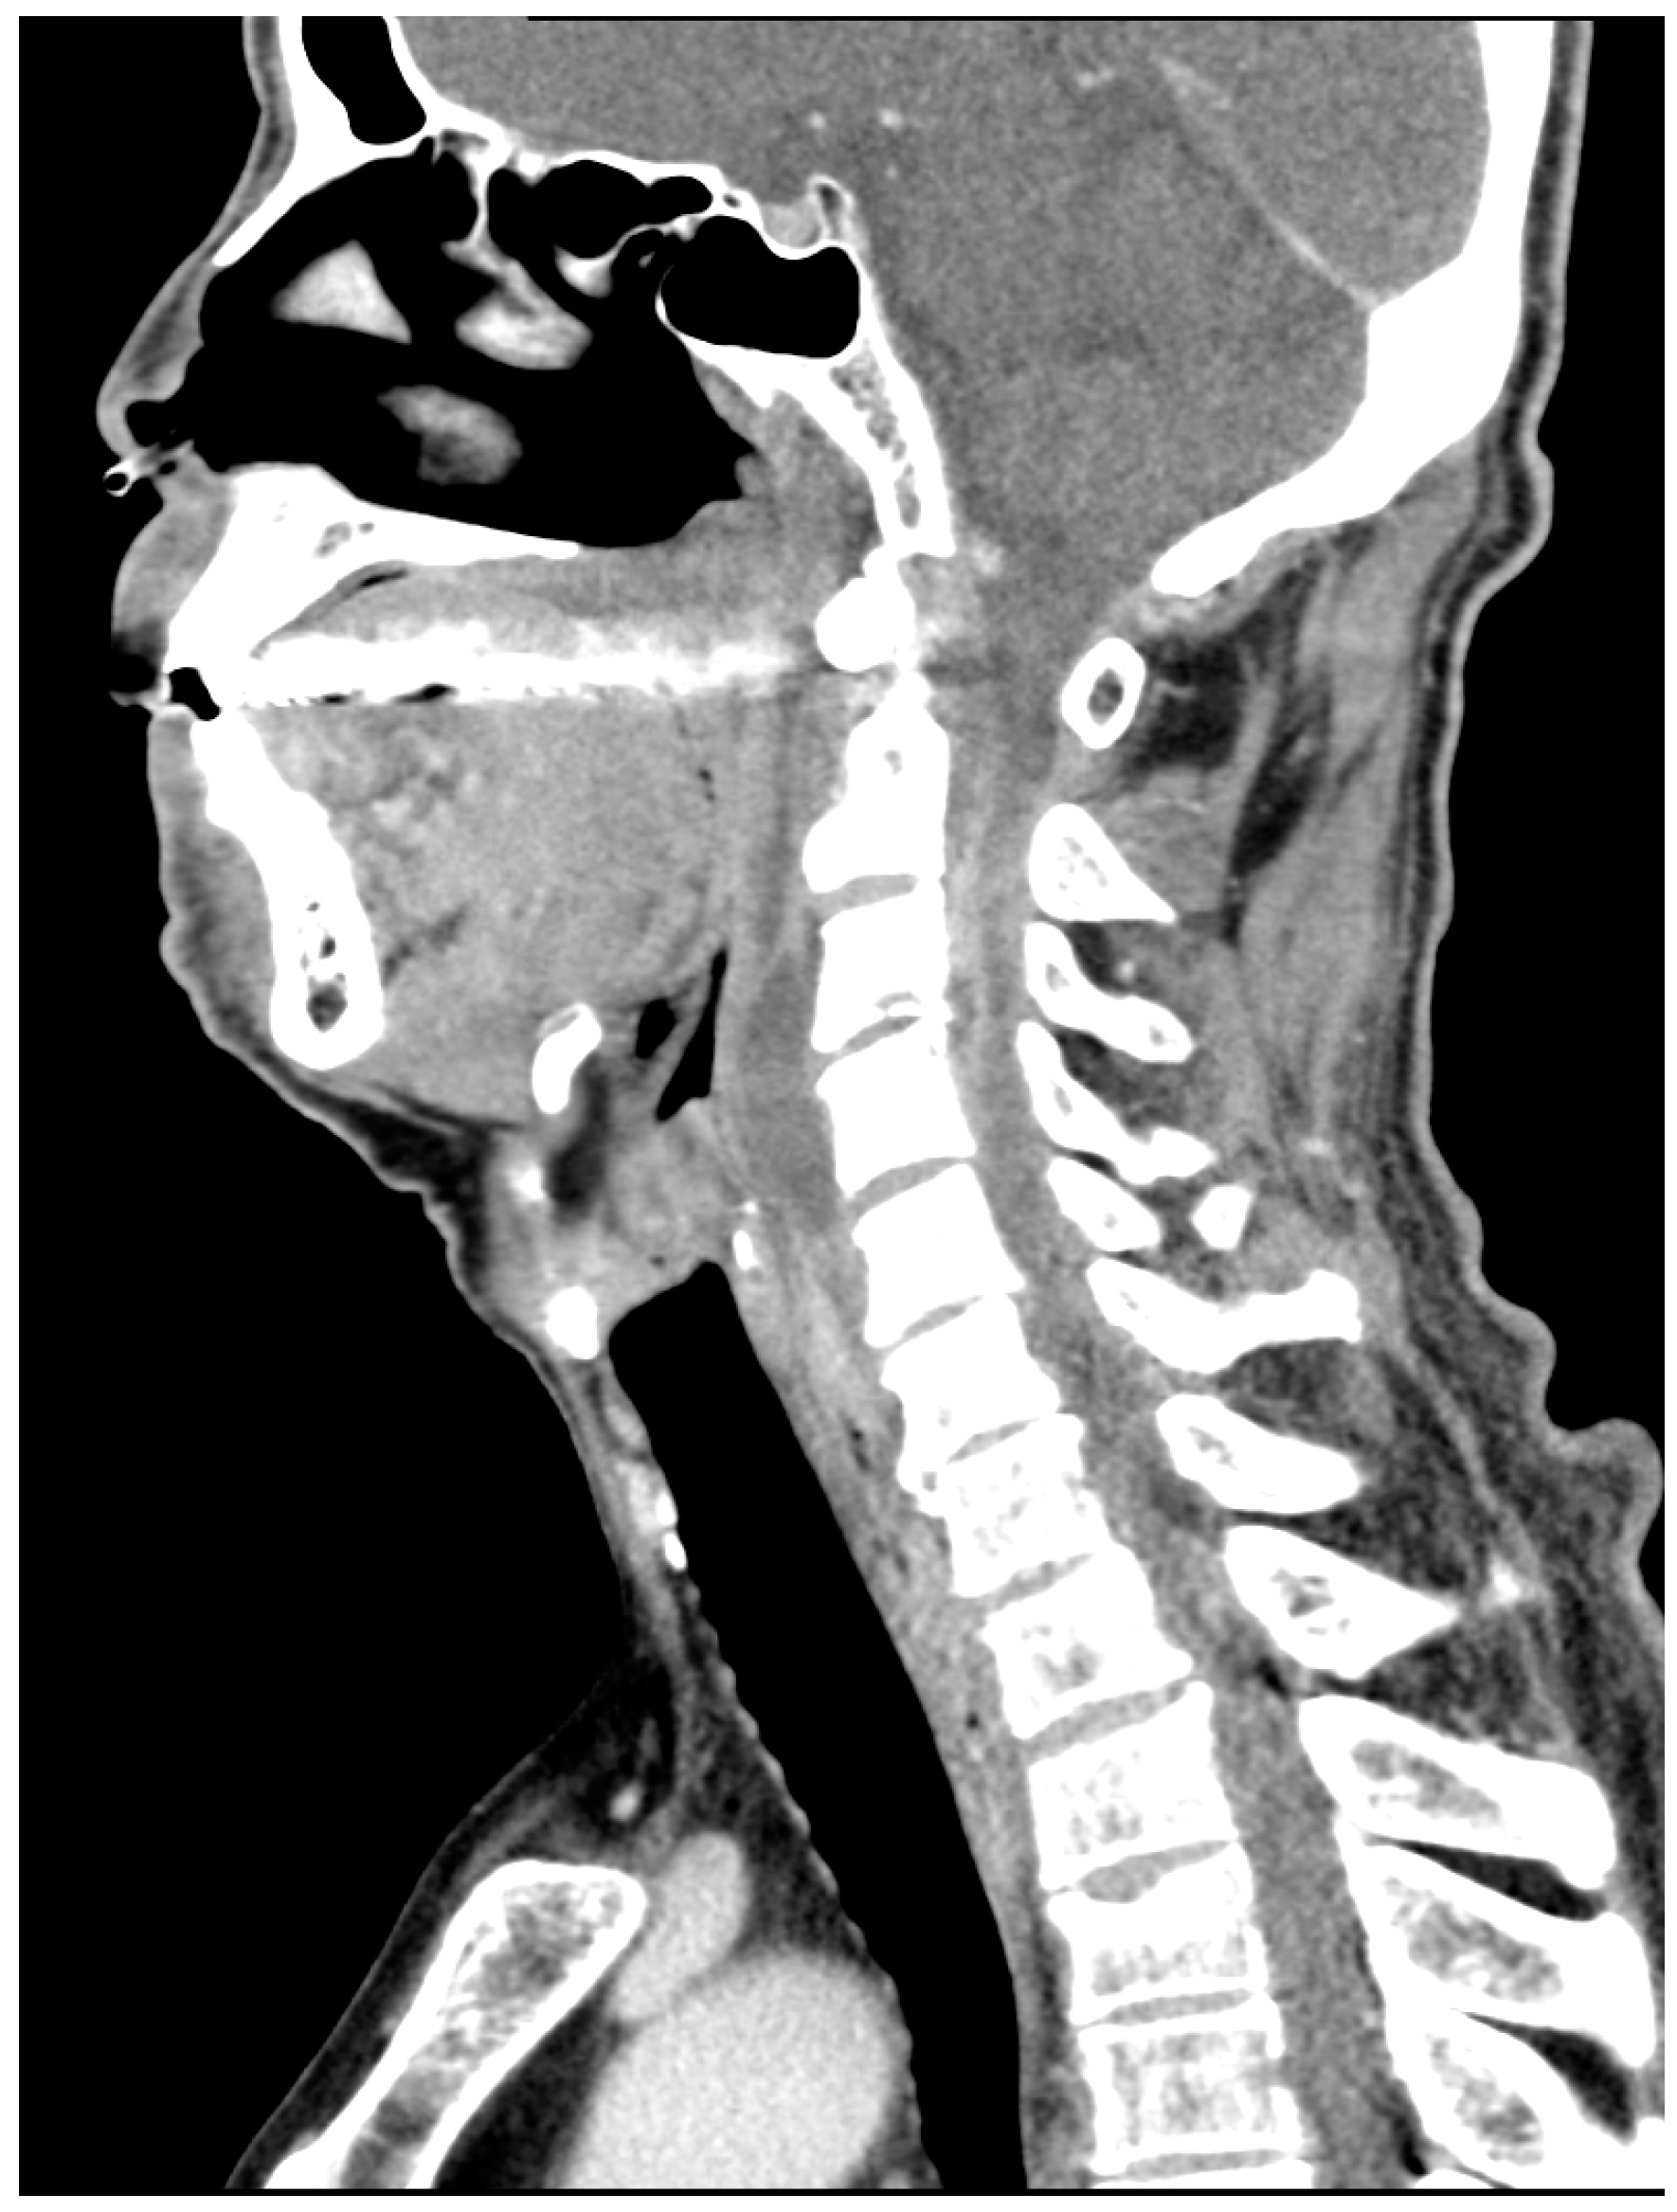

On subsequent contrast-enhanced CT (Figure 2), the collection exhibited peripheral rim enhancement with a progressive mass effect, consistent with superinfection of the pre-existing hematoma.

Figure 2. Enhanced cervical CT on admission (day 0) showing a low-density area with a peripheral enhancement effect. Vertebral body and adjacent soft tissue suggest C3/4 spondylosis and an abscess formation.